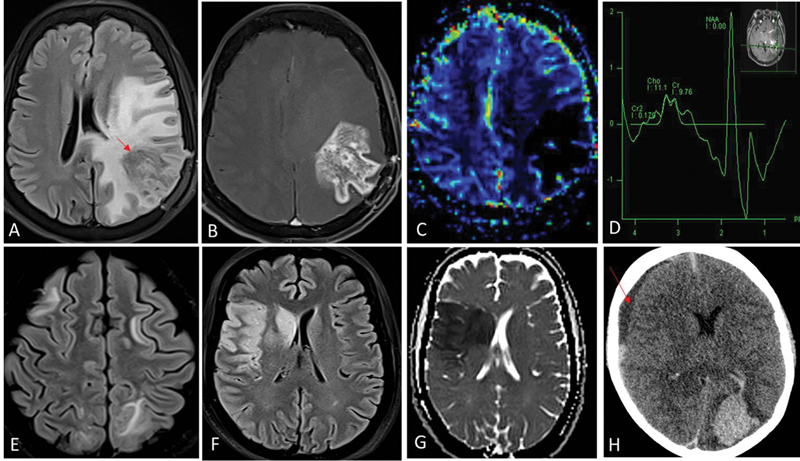

| Fig 1 :Radiation necrosis (A–D). One-year postradiation and temozolomide therapy for left temporal lobe glioblastoma. Fluid-attenuated inversion recovery (FLAIR) shows intermediate-hypointense signal areas (red arrow in A) in the left parietal lobe with surrounding disproportionate white matter edema. Contrast image (B) shows irregular and nodular enhancement (Swiss-cheese pattern) and relative cerebral blood volume (rCBV) perfusion (C) did not show any increased perfusion. Presence of lipid-lactate peak in the corresponding area on magnetic resonance (MR) spectroscopy (D) represents necrosis. These imaging features are typical for radiation-induced injury. Absence of increased choline:NAA ratios (D) further helps exclude tumor progression. Posterior reversible encephalopathy syndrome (PRES) (E). Bilaterally asymmetrical FLAIR hyperintensity in frontoparietal white matter suggestive of vasogenic edema. Acute arterial infarcts (F and G). FLAIR hyperintense areas (F) in right frontoparietal cortex and right basal ganglia due to cytotoxic edema, showing restriction on the corresponding diffusion-weighted image (G) are suggestive of watershed territory infarcts. Intracerebral hematoma (H). Acute hematoma in left occipital lobe appears hyperdense on noncontrast computed tomography (CT). There is an intraventricular extension of bleed into the left lateral ventricle. Subdural hematoma is noted along right cerebral convexity as well (red arrow in H). Chemotherapeutic agents are common inciting factors for PRES, cerebral hematoma, and arterial infarcts.

| Fig 1 :Radiation necrosis (A–D). One-year postradiation and temozolomide therapy for left temporal lobe glioblastoma. Fluid-attenuated inversion recovery (FLAIR) shows intermediate-hypointense signal areas (red arrow in A) in the left parietal lobe with surrounding disproportionate white matter edema. Contrast image (B) shows irregular and nodular enhancement (Swiss-cheese pattern) and relative cerebral blood volume (rCBV) perfusion (C) did not show any increased perfusion. Presence of lipid-lactate peak in the corresponding area on magnetic resonance (MR) spectroscopy (D) represents necrosis. These imaging features are typical for radiation-induced injury. Absence of increased choline:NAA ratios (D) further helps exclude tumor progression. Posterior reversible encephalopathy syndrome (PRES) (E). Bilaterally asymmetrical FLAIR hyperintensity in frontoparietal white matter suggestive of vasogenic edema. Acute arterial infarcts (F and G). FLAIR hyperintense areas (F) in right frontoparietal cortex and right basal ganglia due to cytotoxic edema, showing restriction on the corresponding diffusion-weighted image (G) are suggestive of watershed territory infarcts. Intracerebral hematoma (H). Acute hematoma in left occipital lobe appears hyperdense on noncontrast computed tomography (CT). There is an intraventricular extension of bleed into the left lateral ventricle. Subdural hematoma is noted along right cerebral convexity as well (red arrow in H). Chemotherapeutic agents are common inciting factors for PRES, cerebral hematoma, and arterial infarcts.